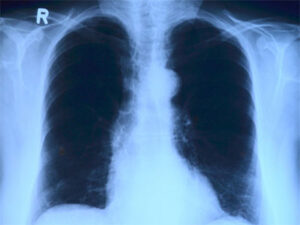

Рентген грудной клетки не видит каждый 4-й рак легких

Ученые из университетов Лидса и Экзетера выяснили, что рентгеновские снимки легких не распознают злокачественные новообразования легких почти у каждого 4-го пациента. В частности, рентгеновские установки пропустили 23% всех опухолей, хотя рентген остаётся одной из основных методик диагностики смертельно опасной болезни. … Читать далее →